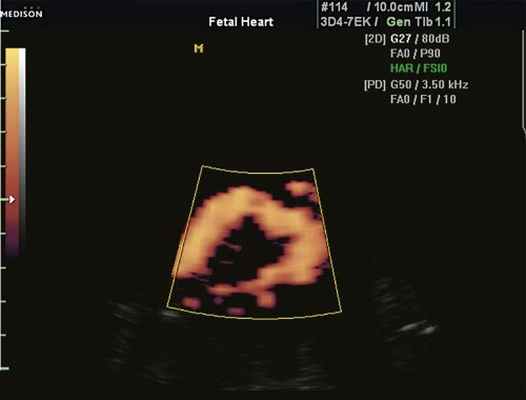

Рис. 1. Восходящий отдел, дуга и нисходящий отдел аорты плода в режиме энергетического допплера в норме.

Согласно "теории дуктальной ткани" коарктация аорты возникает в результате миграции гладких мышечных клеток протока в предуктальную аорту, с последующей констрикцией и сужением просвета аорты [4]. При формировании коарктации аорты в области перешейка сохраняется сужение различной протяженности и формы (рис. 2, 3). Наиболее часто это проявляется в виде локальной перетяжки, выше или ниже которой диаметр аорты сохраняется в норме.

Такие прoтиворечивые результаты можно объяснить гемодинамической теорией [16, 17]. Внутриутробно в восходящий отдел аорты поступает 50% суммарного выброса крови, в нисходящую - 65%, а через перешеек аорты всего лишь 25%. Исходя из уменьшенного объема кровотока возникает его физиологическое сужение, которое усугубляется лишь после рождения.

Допплеркардиография, позволяющая оценить кровоток, информативна лишь при выраженном сужении аорты [18]. При этом возникает обратная зависимость максимальной скорости кровотока в восходящем и нисходящем отделах аорты. В норме скорость в восходящем отделе немного преобладает над скоростью нисходящего отдела.